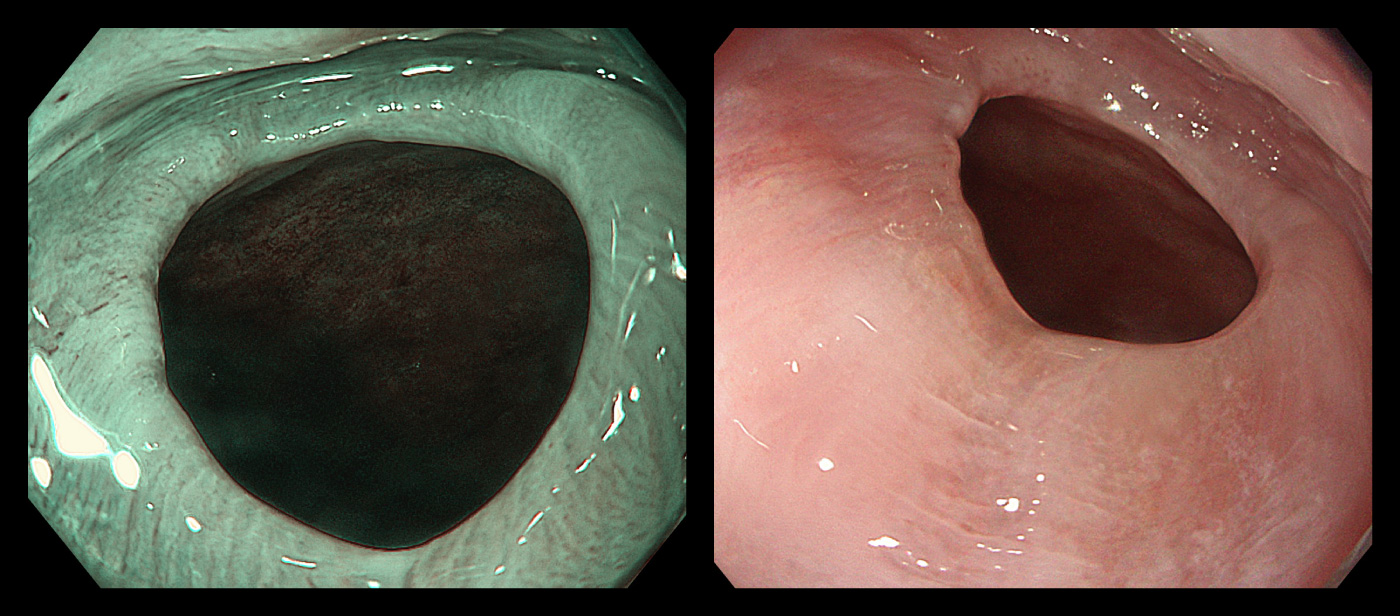

左:ピロリ菌感染を主因として発生した胃潰瘍/

右:ピロリ菌感染を主因として発生した十二指腸潰瘍